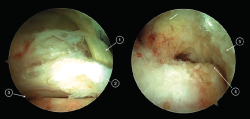

La sección del tendón FHL debe ser cuidadosa, con el objetivo de no poner en riesgo el paquete neurovascular tibial. La longitud mínima ideal del tendón FHL para su transposición al hueso calcáneo es de 15 mm. Antes de realizarse la sección del tendón, debe pasarse una sutura a su alrededor que permita con su tracción obtener la mayor longitud posible de tendón (Figura 2). Si al mismo tiempo de la tracción de la sutura se realiza una flexión plantar del tobillo y del hallux, aún se alcanzará mayor exposición del tendón, lo que permitirá conseguir mayor longitud del tendón.

Figura 2. Una sutura es pasada alrededor del tendón del flexor hallucis longus (FHL) para traccionarlo.

De acuerdo con las zonas descritas del tendón FHL(11), el tendón puede seccionarse en la zona 1 o 2. En la zona 1, el tendón se secciona justo antes de su entrada en la vaina fibro-ósea y con la ayuda de un bisturí o tijeras artroscópicas introducidas a través del portal endoscópico posterolateral. Alternativamente, el FHL puede seccionarse en su zona 2 a su paso bajo el sustentaculum tali. En este último caso, el artroscopio debe introducirse en la vaina fibro-ósea del tendón de FHL y, bajo visión artroscópica directa, el tendón se secciona con la ayuda de un bisturí de cirugía percutánea (bisturí de percutánea número 64) (Figura 3).

Figura 3. Sección del tendón flexor hallucis longus (FHL) en la zona 2. El artroscopio es introducido en la vaina fibro-ósea del tendón de FHL, el punto de sección es identificado con una aguja (visión superior), después es seccionado con un bisturí de cirugía percutánea (visión inferior).